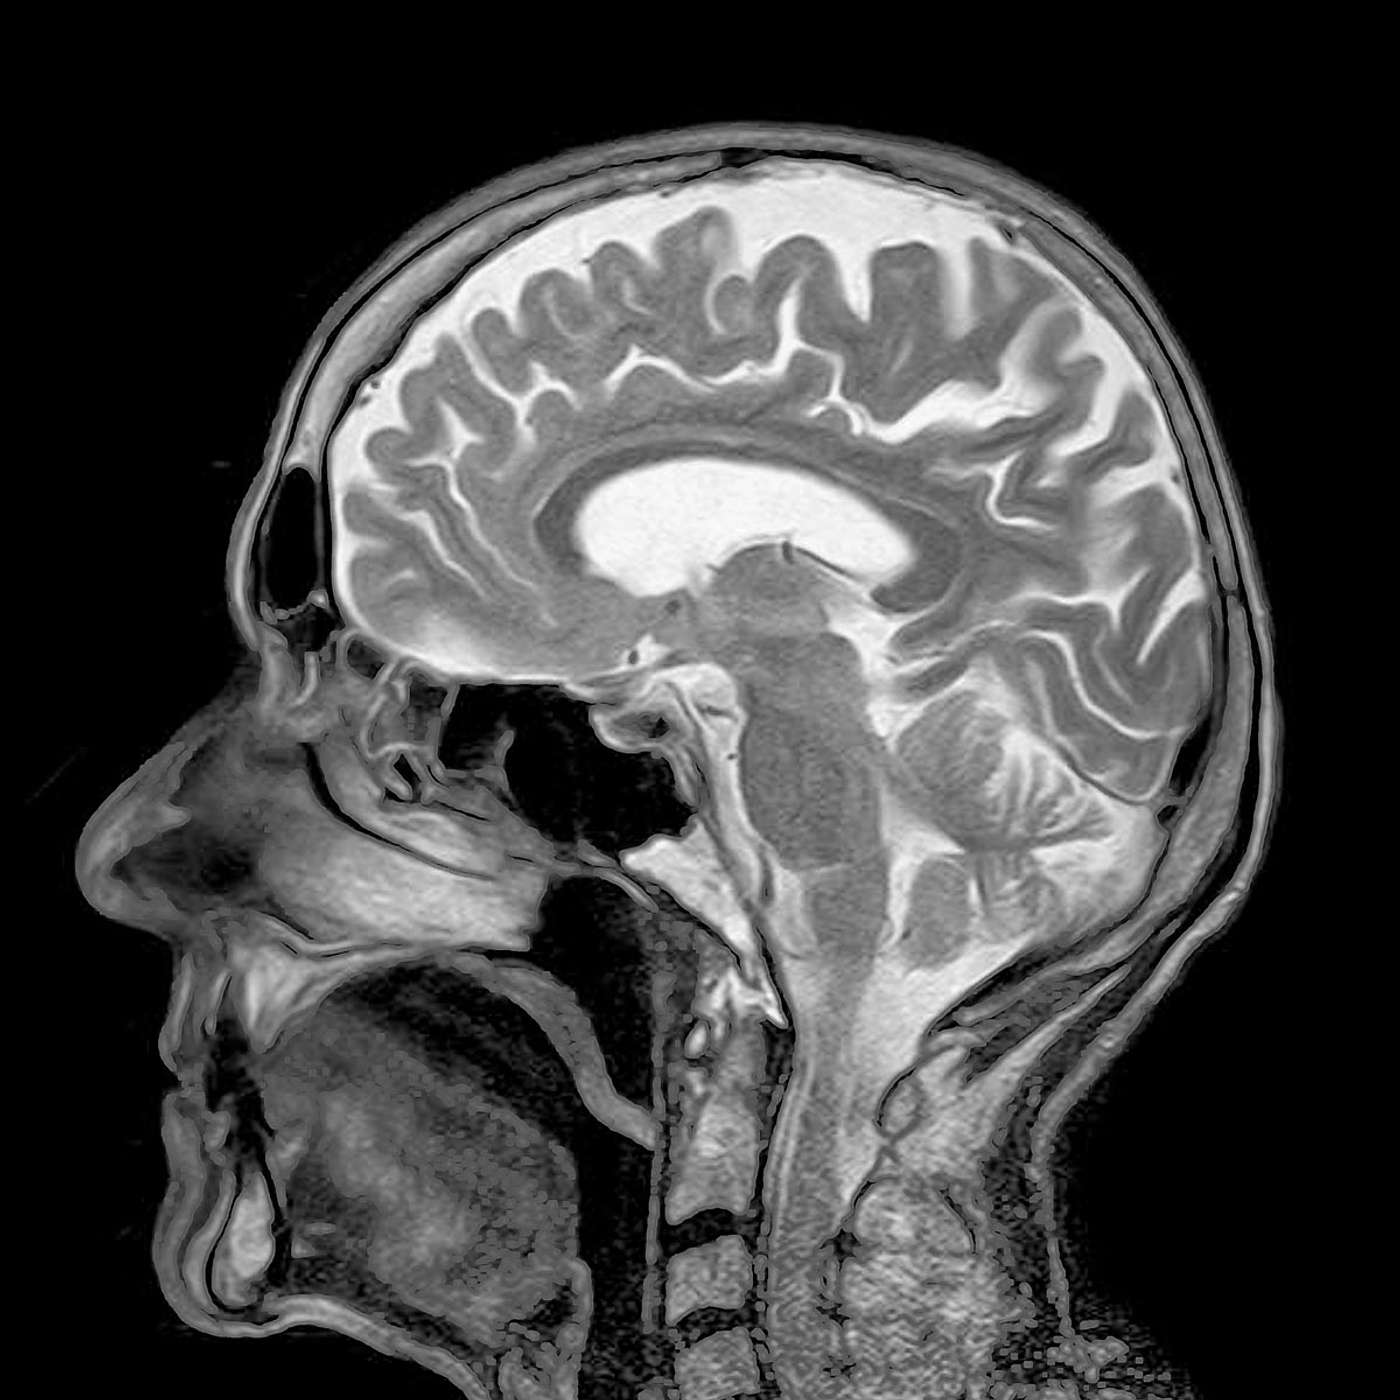

Many of us have been in a medical scanner and benefited from its use in medical diagnostics. But how many of us have considered how it works? The maths behind modern medical imaging (showing how CAT, MRI and Ultrasound scanners work) will be explained, showing how mathematics done in 1915 is now saving countless numbers of lives.

Recent advances in mathematics are leading to much better images for doctors to use for their diagnoses; and similar methods and ideas are used in diverse applications such as remote sensing, oil prospecting, crime detection, studying bees and saving the whales.